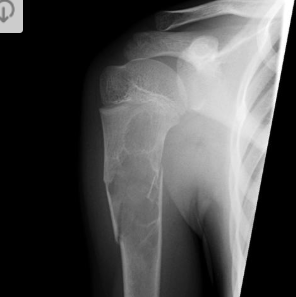

Condroblastoma da escápula